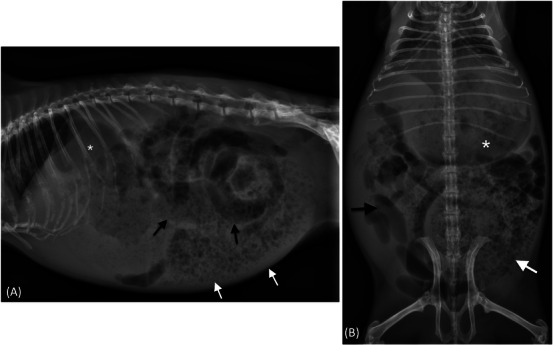

A 6-year-old intact male guinea pig was presented for acute abdominal pain, anorexia, and absence of ambulation for 12 h. Radiographs revealed moderate gastric dilation and multifocal marked small intestinal gas dilation. Ultrasonography showed a focally dilated jejunal loop with abrupt narrowing and torsion, with a mesenteric vascular "whirl sign". The aborad jejunum was empty. Surgery revealed a focal mesenteric torsion with associated segmental jejunal torsion and consequent jejunal occlusion. A cardiopulmonary arrest occurred during the surgery. This is the first report of diagnostic imaging findings associated with mesenteric torsion in a guinea pig.